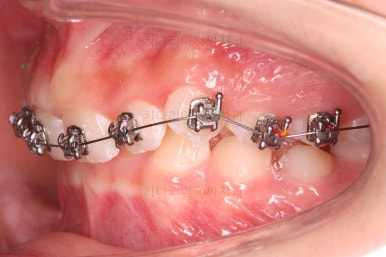

초진 시 입안의 모습입니다.

앞니가 안으로 굽어 들어간 양상인데요. 흔히 "옥니"라고 표현합니다.(뻐드렁니의 반대개념)

전반적으로 치열이 삐뚤삐뚤하고요.

오른쪽 상단 사진을 보시면 어금니의 높이와 앞니의 높이의 차이가 많이 나요.

앞니가 솟구쳐 있는 양상인데요.

그 이유 때문에 어금니로 다물었을 때 위아래 앞니가 많이 겹쳐서 아래 앞니가 아예 보이지 않는 상황이었어요.

이를 "과개교합"이라고 표현합니다.

그리고 전반적으로 아래 치열이 윗니에 비해 뒤로 밀려 있어서, 어금니의 맞물림이 좋지 못하고 듬성듬성해 보이는 상황이었어요.